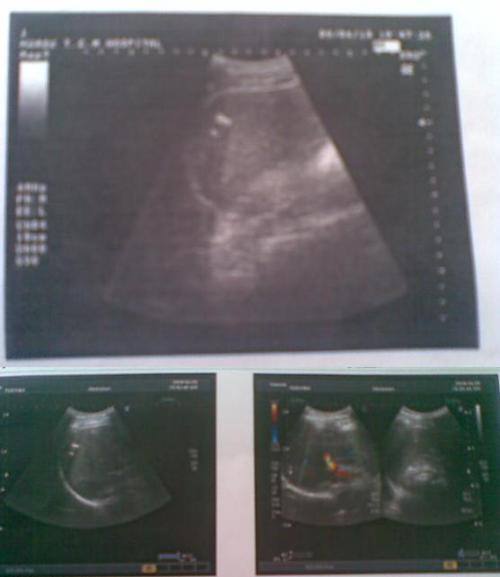

胆囊B超

胆囊B超,胆囊

多发性结石

胆囊蛔虫b超图片

胆囊蛔虫死体b超图片